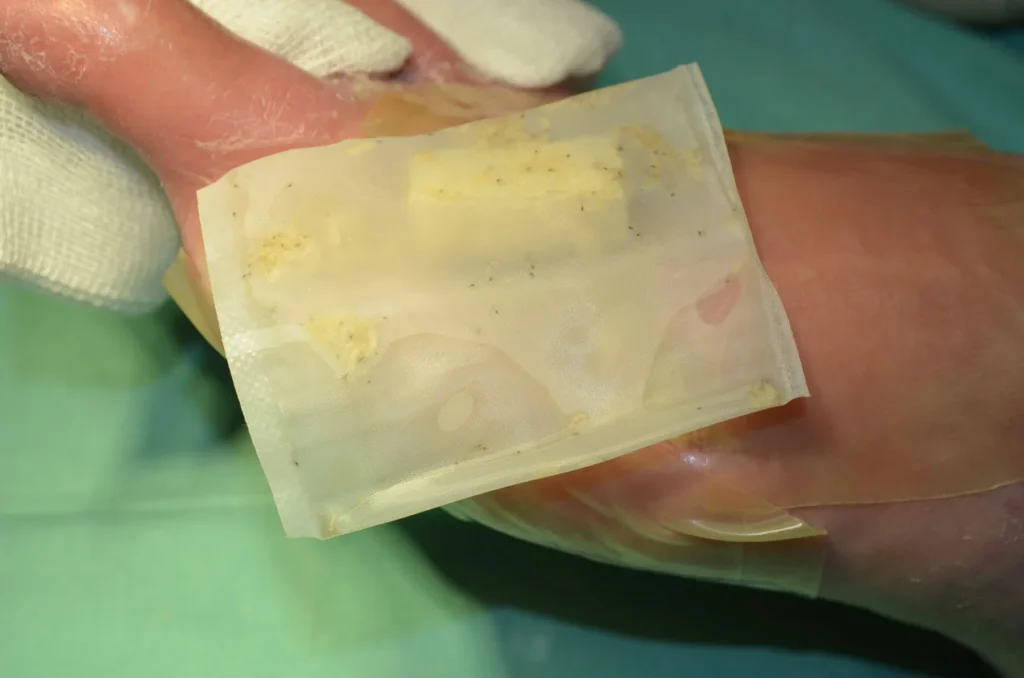

Alginatkompressen bestehen aus tamponierbaren, wirkstofffreien Calcium-Alginat-Fasern, die sich im Austausch mit Natriumsalzen von Blut oder Exsudat in ein hydrophiles Gel umwandeln. Einige Alginate bleiben jedoch form- und strukturstabil, wandeln sich also nicht in ein Gel um (Cutimed Alginate ![]() (3)). Je nach Wundverhältnis finden sie ihren Einsatz.

Infolge des intrakapillären Saugvermögens werden nicht nur überschüssiges Wundexsudat, sondern auch Keime und Detritus aufgenommen und mit jedem Verbandwechsel mechanisch entfernt. Alginate, mit oder ohne Zusatz, dienen als Wundfüller und exsudataufnehmende Verbandstoffe, die auch die Verbandwechselintervalle verlängern können. Die Besonderheiten einzelner Produkte sind anschließend noch einmal aufgeführt.

Hauptanwendungsgebiet: Wunden mit zerklüftetem Wundgrund. Durch Gelierung des Alginates wird eine Traumatisierung von Granulationsgewebe vermieden. Der alleinige Einsatz bei infizierten Wunden ist nicht möglich. Achtung beim Einsatz von Alginaten in Fistelgängen o.ä. Stark gelierende Alginate lassen sich nur schwerlich entfernen. Trockene Wunden und Nekrosen werden nicht mit Alginaten versorgt.